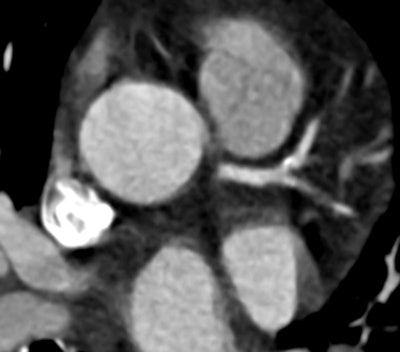

![]() |

| Compared to filtered back projection reconstruction (above), use of the iTRIM algorithm improves temporal resolution and renders a more diagnostic image. |